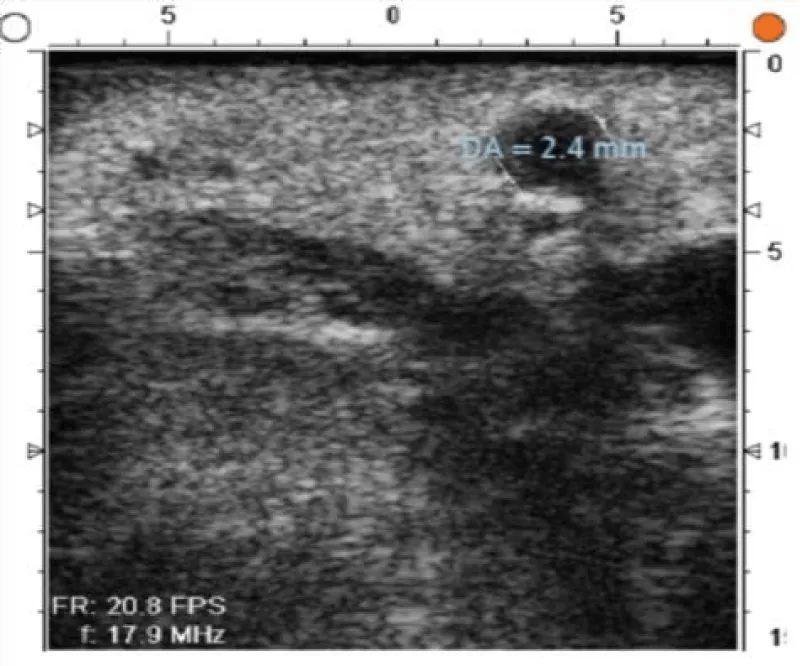

Figure 6: Anterior descending coronary artery with 2,4mm diameter and an intact arterial wall.

Download Image